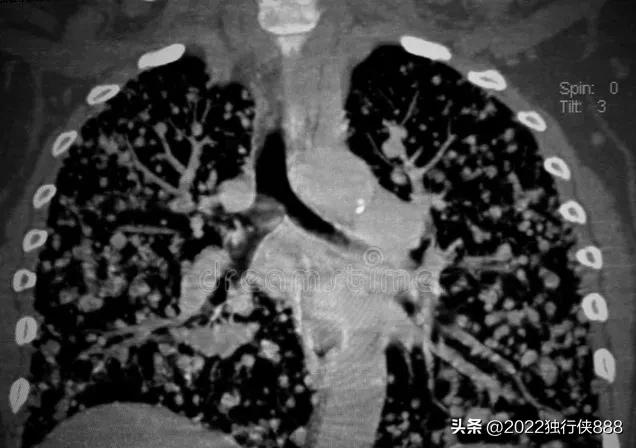

过年前,因胸闷气短难受,带去三甲医院心内科就诊,做了心脏加强CT,刚做完检查,报告都还没出来,检查医生就让先去找呼吸科看,说把就诊卡给医生,医生看得到片子。

先找的开单的心内科医生,看了一下片子说,这个真的要找呼吸科医生,心脏没问题,肺部有问题。

呼吸科医生看后,给了两个可能性:肺癌?或者肺结核?需要进一步检查,该医院没有床位,建议报告出来后,转到肿瘤医院检查。